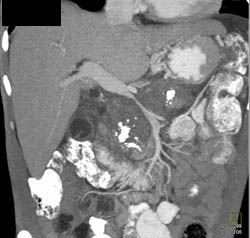

Cystadenoma of the Pancreas